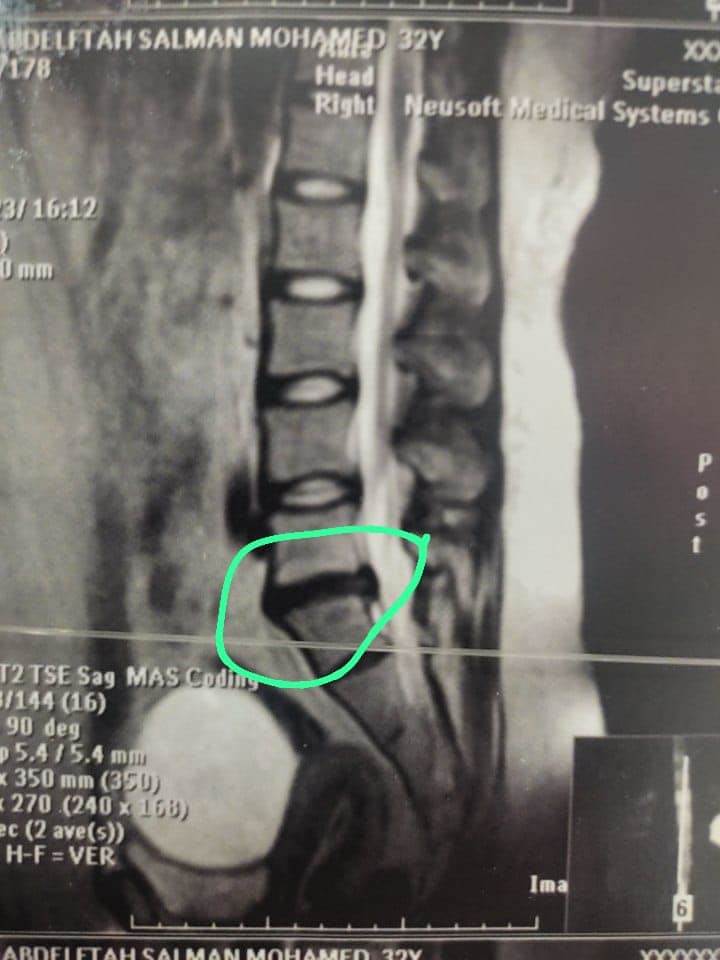

وقال الدكتور تامر حمدى أحمد مدير عام مستشفى بئر العبد التخصصى (في بيان) أنه تحت رعاية الدكتور خالد عبدالغفار وزير الصحة والدكتورة مها إبراهيم رئيس أمانة المراكز الطبية المتخصصة، والدكتور خالد الدرندلى رئيس جامعة الزقازيق والدكتور أحمد عنانى عميد كلية طب الزقازيق والدكتور محمود مصطفى طه رئيس قسم جراحة المخ والأعصاب بجامعة الزقازيق.. حيث قام الدكتور محمود محمد متولى مدرس مساعد جراحة المخ والأعصاب بجامعة الزقازيق بمساعدة الدكتور محمود الوكيل مدرس التخدير بالقصر العينى جامعة القاهرة باجراء جراحة لمريضة عمرها ٤٠عاما كانت تعانى من آلام شديدة وعرق نسا بالساق اليسرى تمنعها من المشى وممارسة حياتها اليومية بشكل طبيعى، وكانت لا تستجيب للعلاج، وأظهر الرنين المغناطيسى وجود انزلاق غضروفى ما بين الفقرات الخامسة القطنية والعجزية الأولى واختناق بجذور أعصاب الساق اليسرى، وقد تم تجهيز المريض ودخول العمليات واجراء جراحة لاستئصال الغضروف وتسليك جذور الأعصاب، وذلك من خلال جرح صغير بالظهر لا يتعدى الـ٣ سنتيمترات.